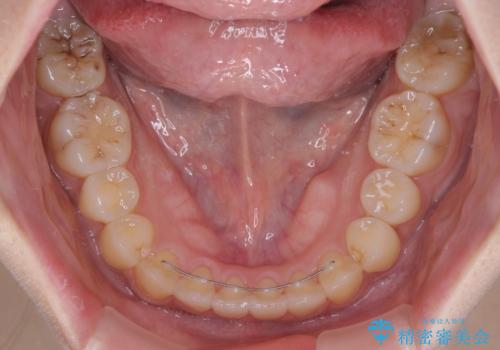

- 八重歯や前歯の捻転とクロスバイトが気になり、インビザラインによる矯正治療を希望して来院された患者様です。

上顎側切歯(上の真ん中から2番目の歯)が舌側転位している場合、無理して動かそうとすると歯髄壊死を起こすリスクが高い印象があります。

インビザライン単体でも治療は可能ですが、安全策としてインビザラインで歯列を移動する前に上顎前歯をワイヤー矯正で整え、その後上下歯列をインビザラインにて矯正治療を行うこととしました。

舌側転位している側切歯特有の、切縁の位置が不揃いであったり、根元が内側に引っ込んだ状態であったりという、インビザライン独特の仕上がりになることなく、きれいに整った歯列とすることができました。